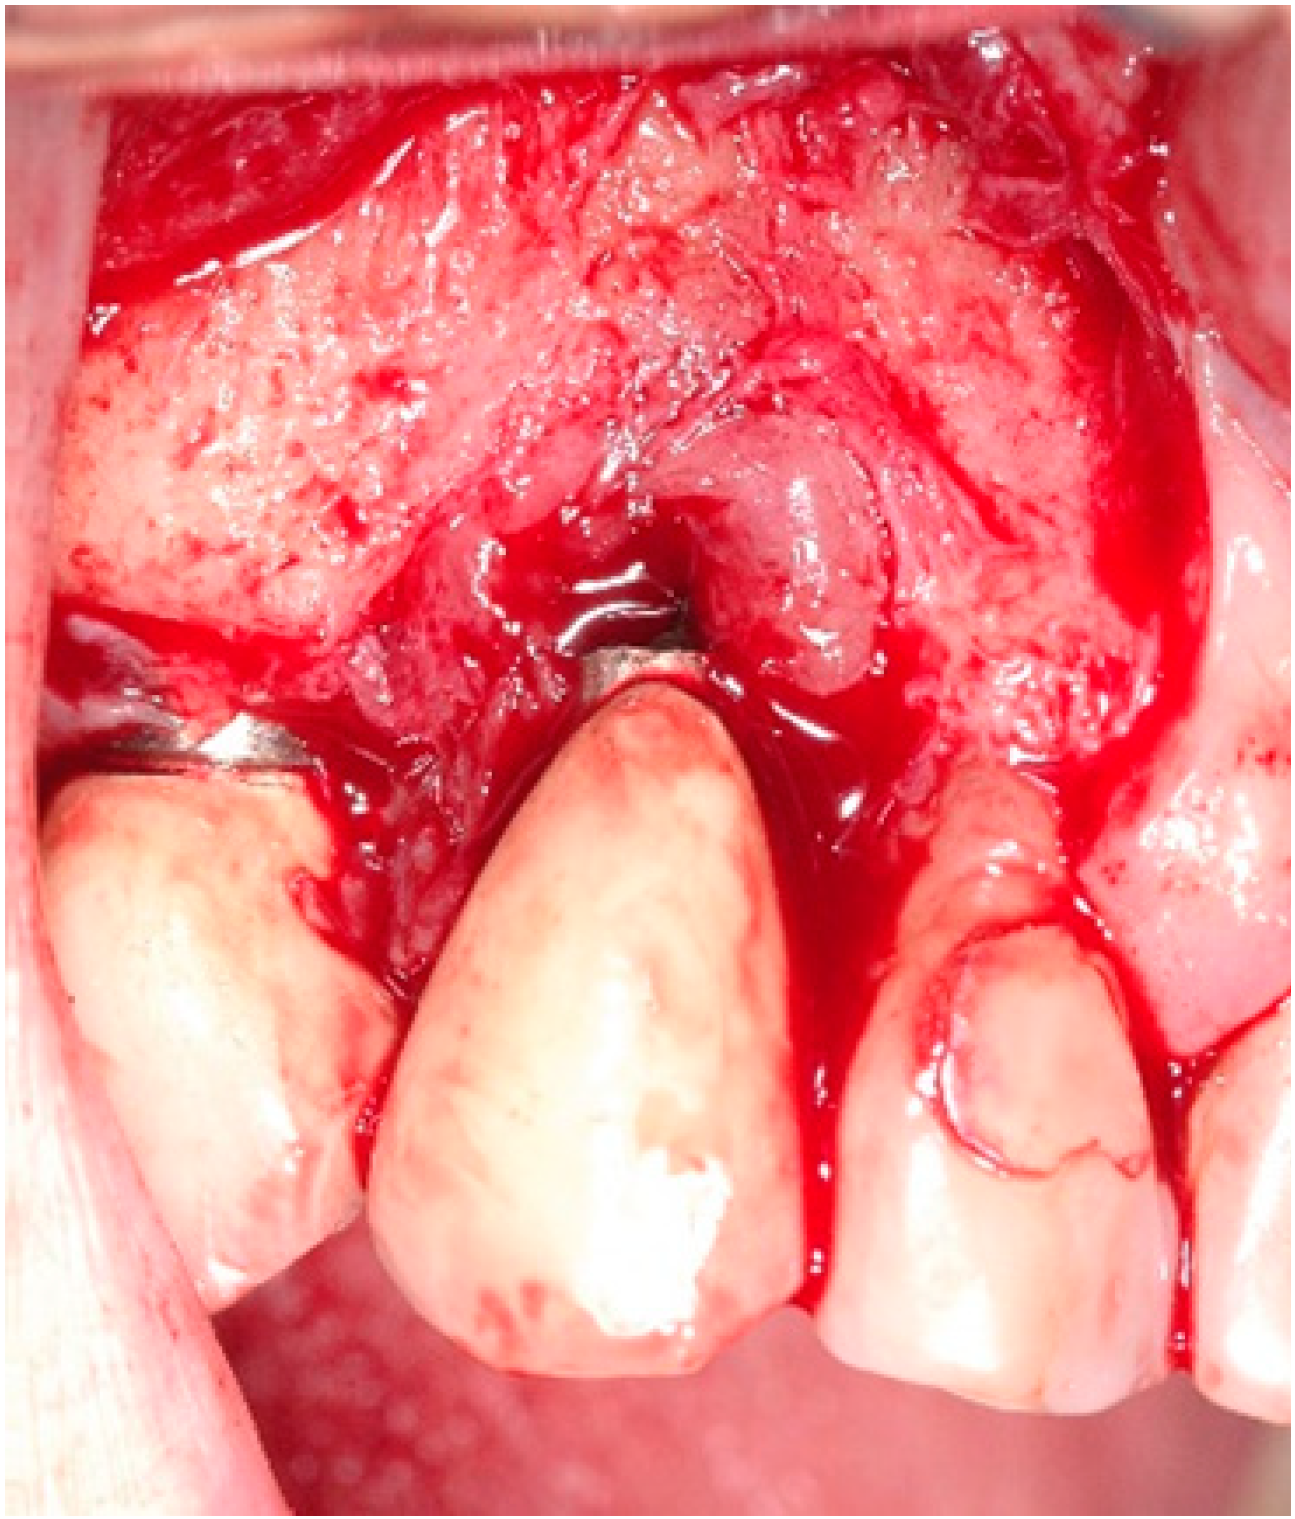

4.1. Surgical Procedure for Open Flap Debridement

4.2. Clinical Case